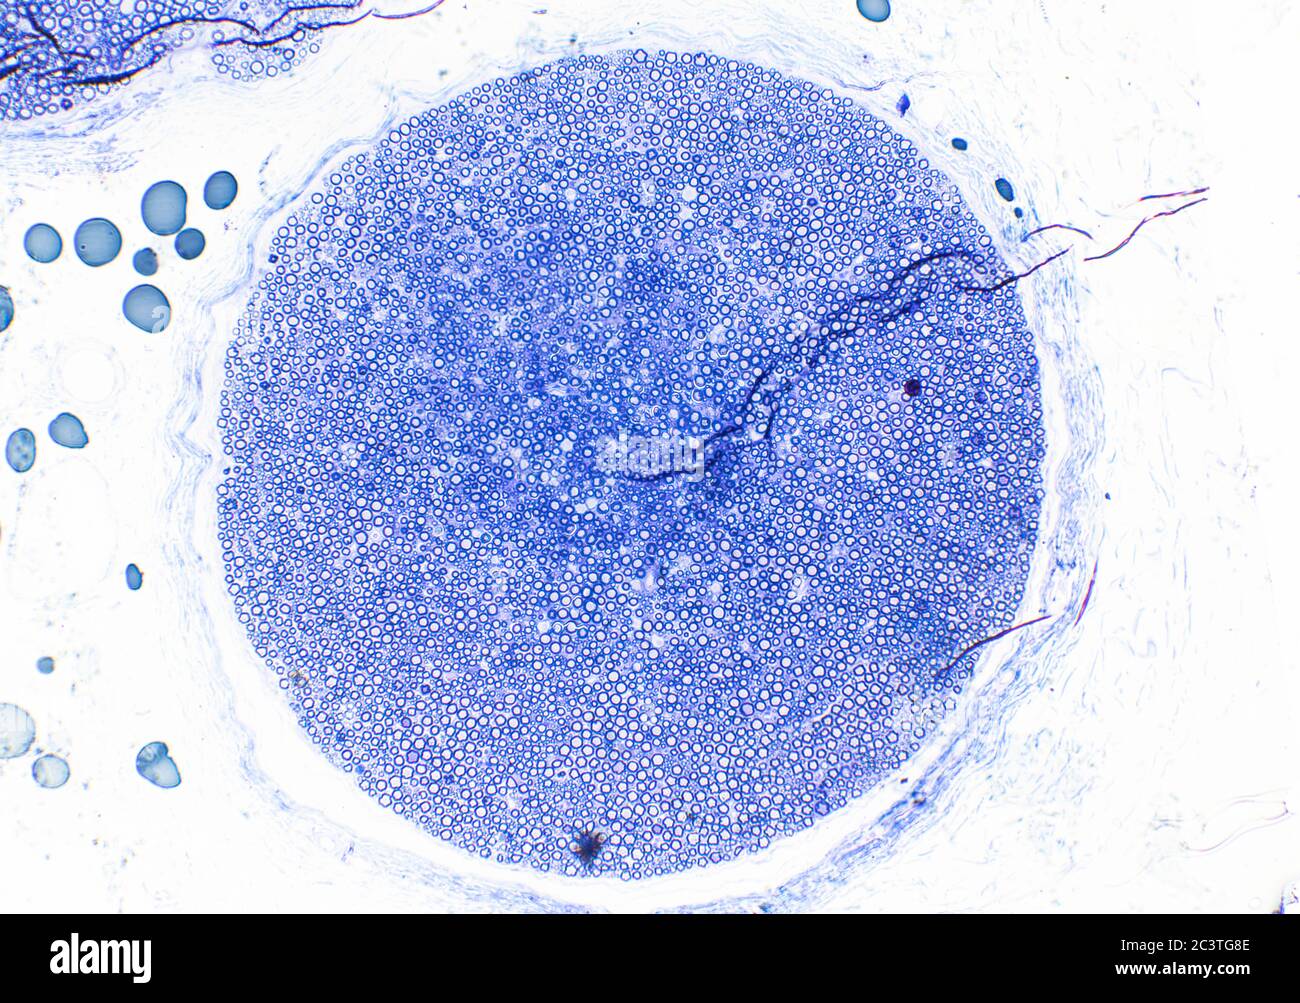

Nerf sciatique de mammifère, coupe transversale, vue au microscope Banque D'Imageshttps://www.alamyimages.fr/image-license-details/?v=1https://www.alamyimages.fr/nerf-sciatique-de-mammifere-coupe-transversale-vue-au-microscope-image363801326.html

Nerf sciatique de mammifère, coupe transversale, vue au microscope Banque D'Imageshttps://www.alamyimages.fr/image-license-details/?v=1https://www.alamyimages.fr/nerf-sciatique-de-mammifere-coupe-transversale-vue-au-microscope-image363801326.htmlRM2C3TG8E–Nerf sciatique de mammifère, coupe transversale, vue au microscope